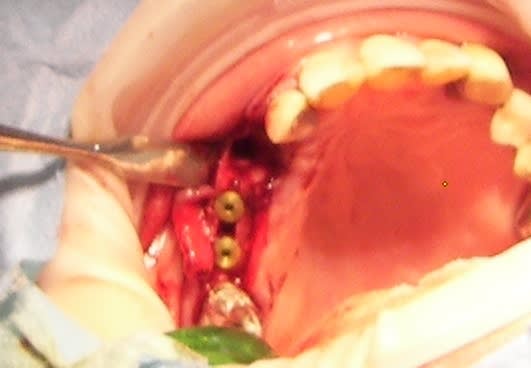

dudule...je suis d'accord avec toi pour la chir muco gingivale...mais il est jeune...et quitte à ouvrir...tu tenterais pas en plus un comblement bio-oss+ membrane pour faire "une régénération osseuse du site" qui te permettait par la suite de lui poser un implant si çà marche, plutôt que lui mutiler ses 21 et 23 qui sont exemptes de soins?

1:greffe gingivale conjonctif enfoui avec repositionnement coronaire au max du lambeau.

2:greffe osseuse en onlay

3:pose d'un mini implant type dentatus avec mise en esthétique immédiate

vu le scan, je propose toujours la même chose: perte de 21 (mais en se servant d'elle pour tracter au mieux os et tissus mous puis greffe onlay et enfin implants.

greffe osseuse en onlay.